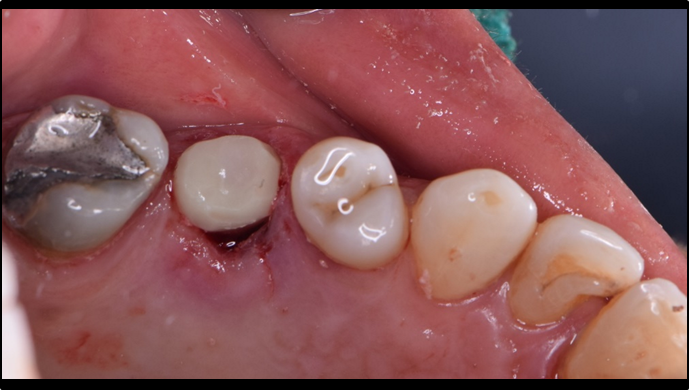

Clinical case: Immediate implant placement using R2GATE Guide & custom healing abutment

- Courtesy of Dr. Sam Omar, Egypt -

Keywords

Dr. Dr. Sam Omar,Digital Guided Surgery,Digital Digital Guided Surgery,Digital ONE-DAY Implant,Maxillary Posterior,#16,Guided surgery,Loading,Flapless,AnyRidge,R2GATE,MEGA ISQ,R2GATE Full surgical kit